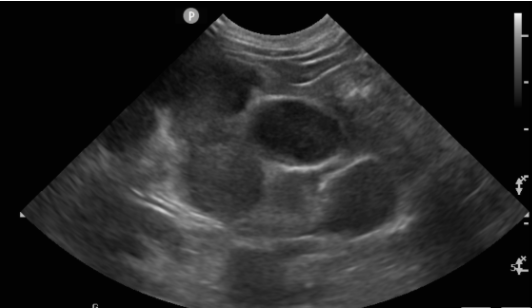

• 貓咪腎臟病 腎臟腫瘤 貓淋巴癌化療

貓咪腎臟病 腎臟腫瘤 貓淋巴癌化療